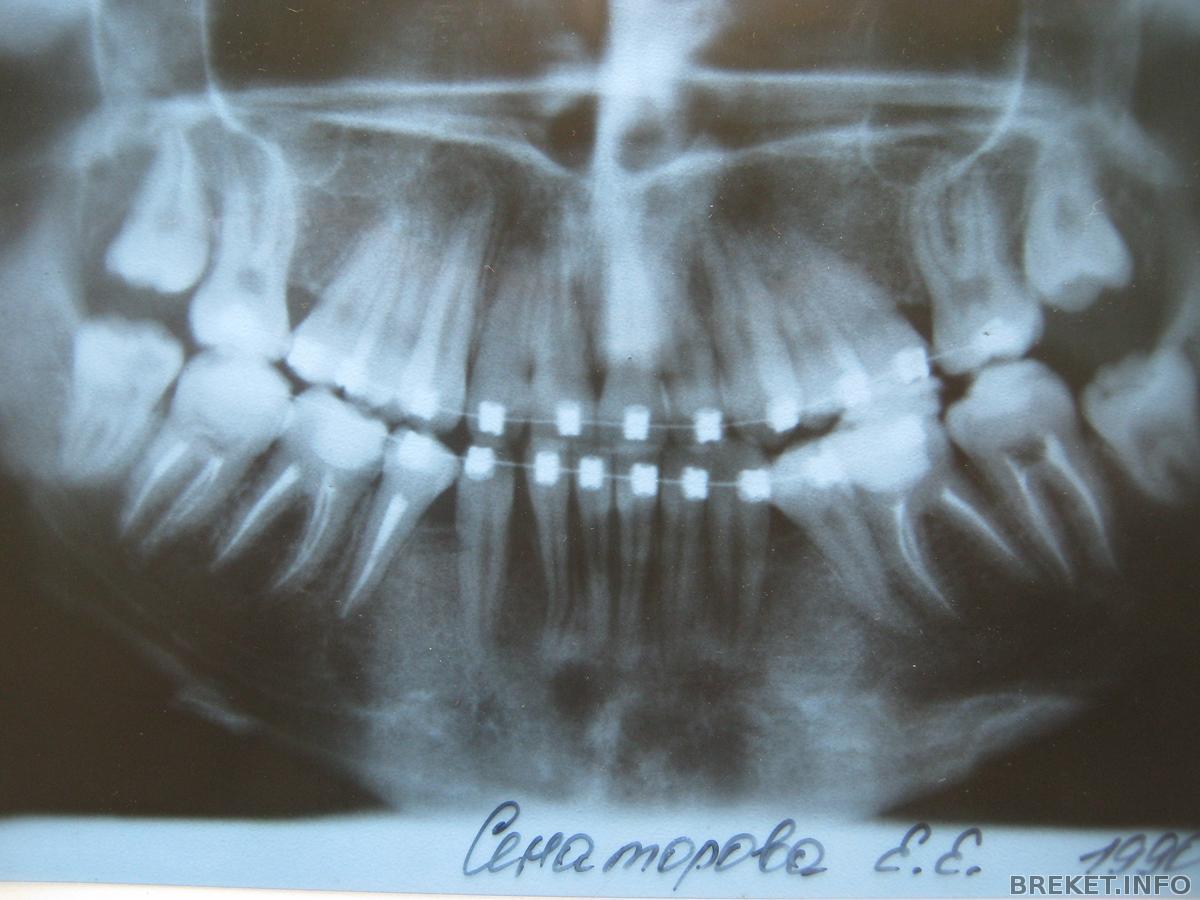

Сегодня обнаружила какую-то белую твёрдую фигнюшку в десне под лункой от зуба 44 о))______________((о

не знаю, когда появилась, мб недавно, мб всегда была... просто как-то не обращала внимания.

А сегодня пальцем нажала - больновато, но по ощущениям сходно с той болью, когда тупо сильно давишь на десну (ну, с зубом внутри), и всё. Если честно, не знаю, что это, но думаю, что просто кость челюсти

маман вообще утверждает, что это КОРЕНЬ СОСЕДНЕГО ЗУБА

Ну не может это быть корень, так далеко уполз от зуба что ли?